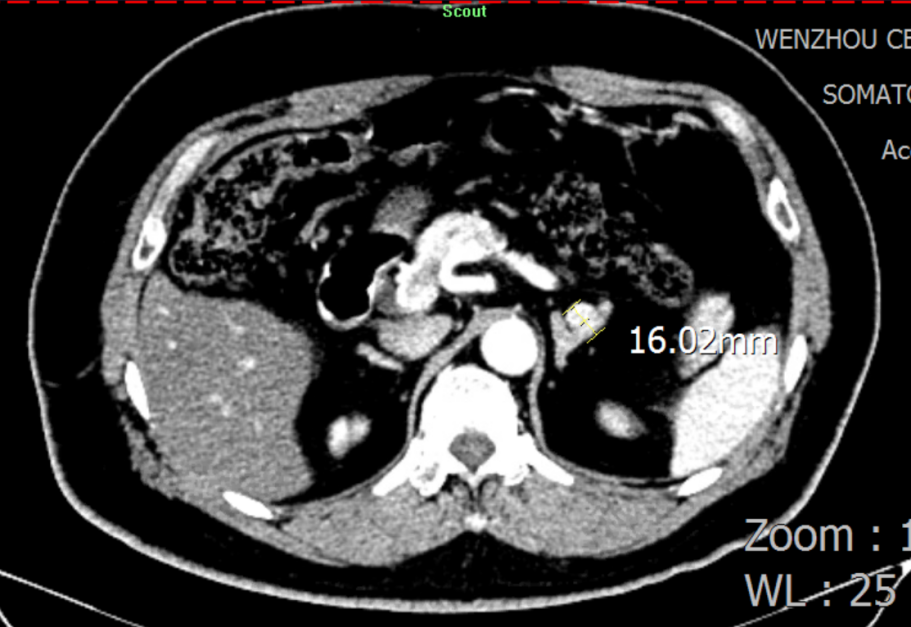

图片3.png

肾上腺增强CT:思量左侧肾上腺结节状增生